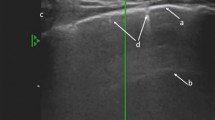

Bedside pleural ultrasound was performed within 12 h of CT acquisition and within 8 h preceding pleural drainage using a Hitachi-405 (Hitachi Medical Corporation, Tokyo, Japan) with a microconvex 5-MHz probe or a HP Sonos 5500 (Hewlett Packard, Andover, MA) with a 3.5-MHz cardiac phased-array probe. Both investigators who performed the ultrasound pleural assessments were blinded to the CT measurements. The physicians who performed the thoracic drainages were blinded to the ultrasound measurements. The pleural cavity was explored on transverse views in supine patients by positioning the probe in each paravertebral intercostal space (Fig. 1). In order to facilitate PE measurements, the probe was slipped between the patient's back and mattress. The lower and upper intercostal spaces where PE was detected were drawn on the patient’s skin. The PE paravertebral length (L US) was measured between these two points (in cm). Ultrasound PEV (PEVUS) was calculated by multiplying its length (L US) by its cross-sectional area (A US), measured at half the distance between its apical and caudal limits, in a strict transversal plane, at end-expiration. A US was measured as follows: after freezing the image on the screen, the area of PE was manually delineated, and the area was automatically calculated using the ultrasound scanner software (Fig. 2). A US was considered as the mean of three consecutive measurements.

Schematic procedure to quantify PEV with the new formula assessed by ultrasound. The upper (1) and lower (2) paravertebral intercostal spaces where PE is detected are drawn on the patient’s skin. The PE paravertebral length (L US) was measured between these two points (in cm) (3). The middle of the PE height was located (4). At this point, the probe was applied to the skin in a strict transversal plane, at end-expiration, as posterior as possible. The cross-sectional area at mid length (A US) was measured: after freezing the image on the screen, the PE area was manually delineated, and A US was automatically calculated using the ultrasound scanner software (in cm2). A US was considered as the mean of three consecutive measurements. Ultrasound PEV (PEVUS, in ml) was calculated by multiplying L US by A US